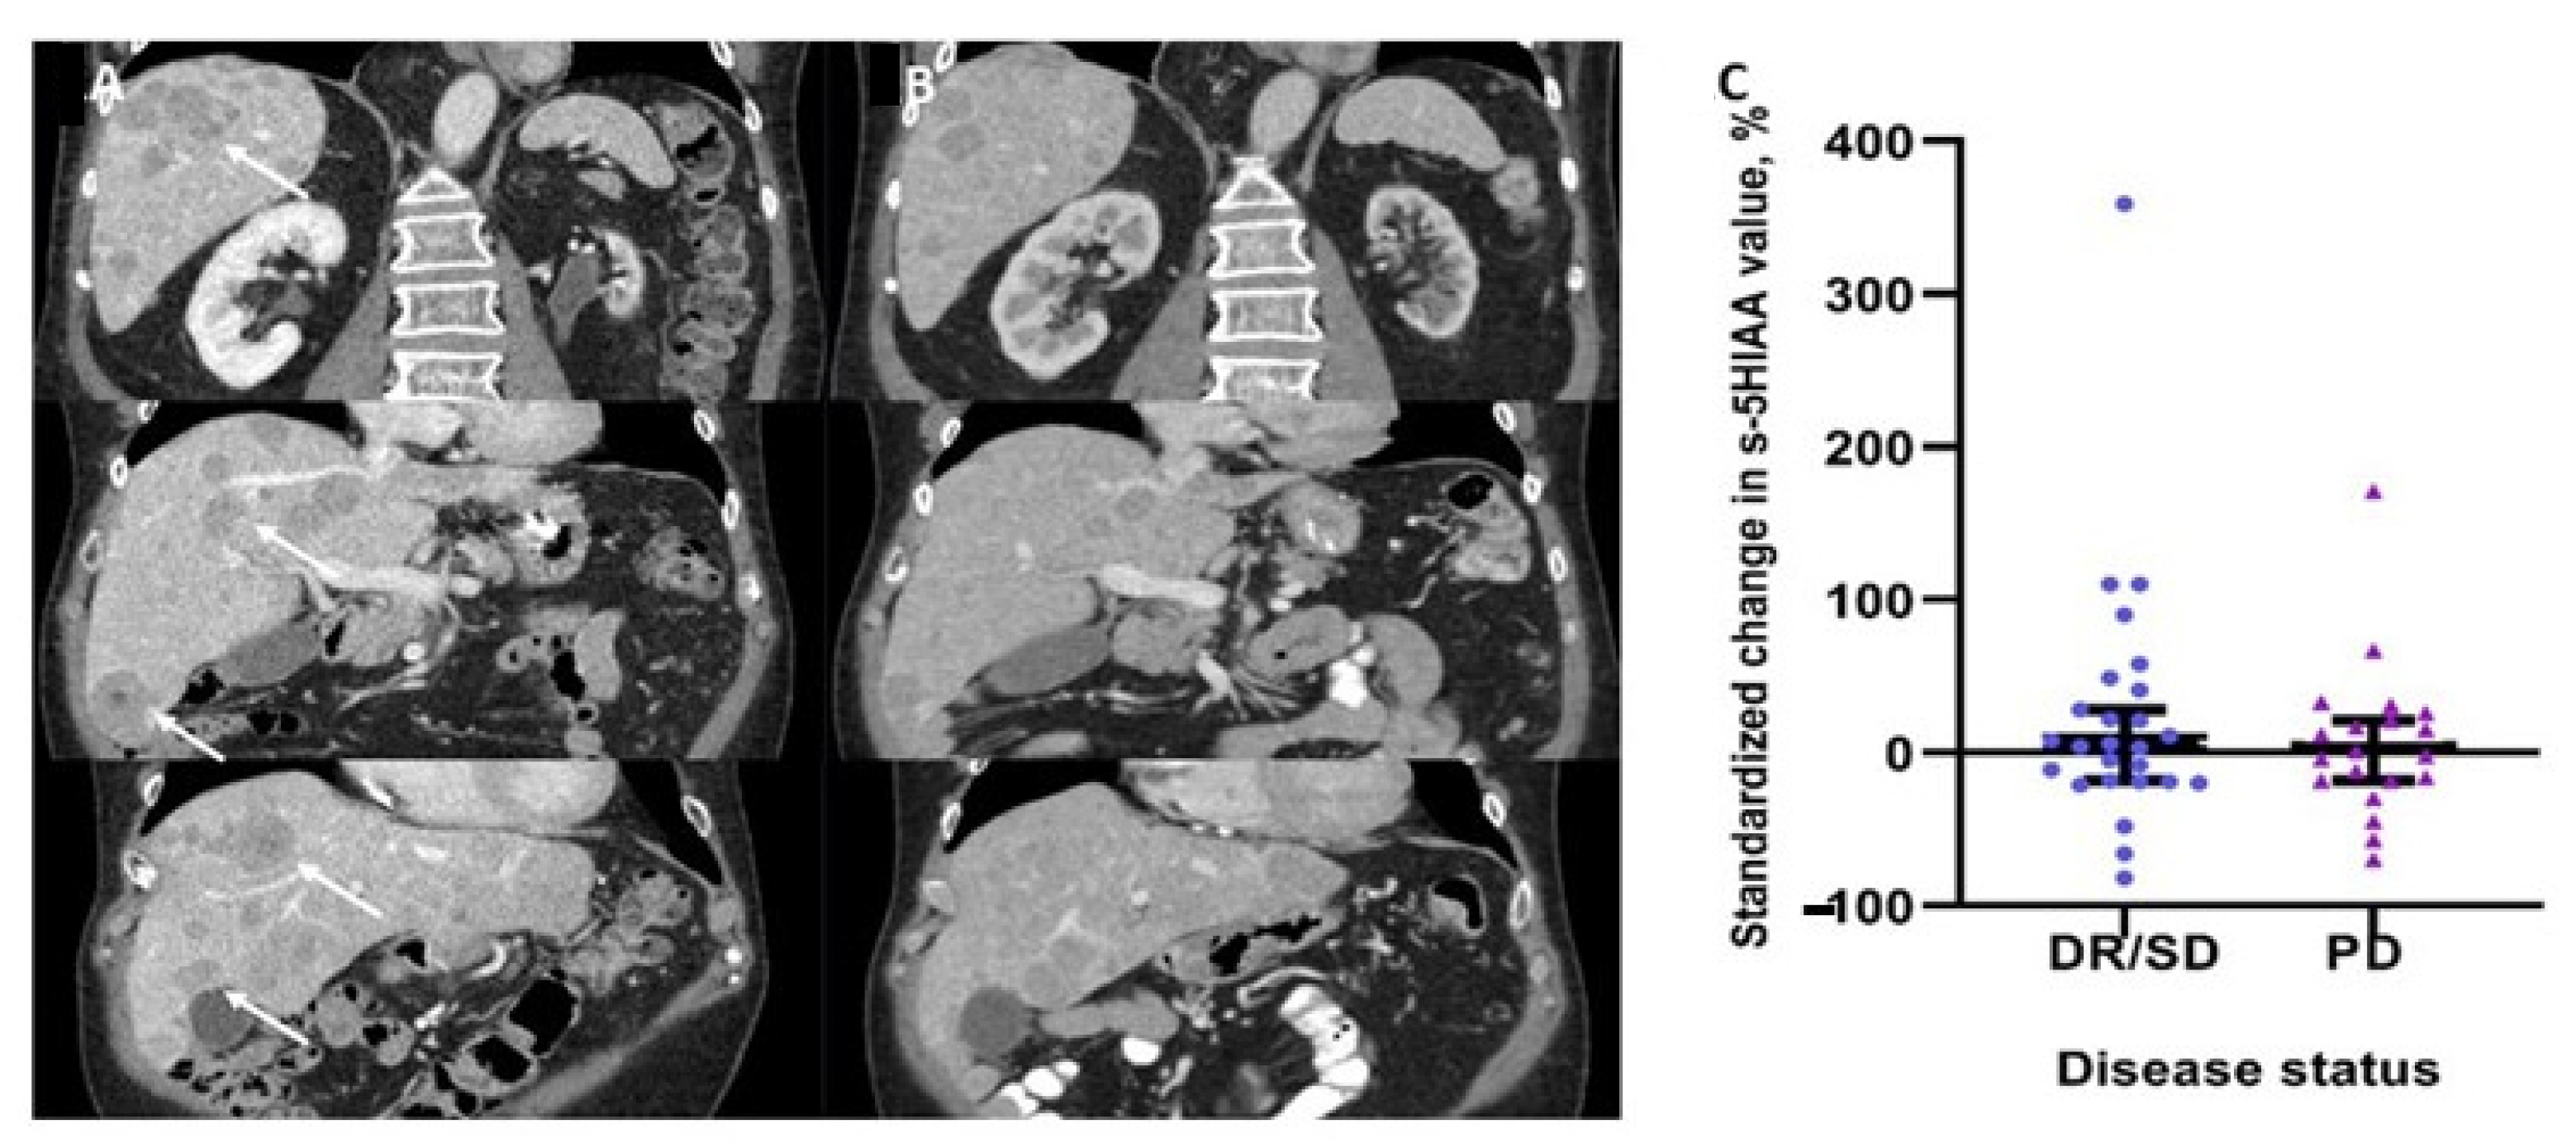

3.2. Changes in Serum 5HIAA Levels and Disease Status